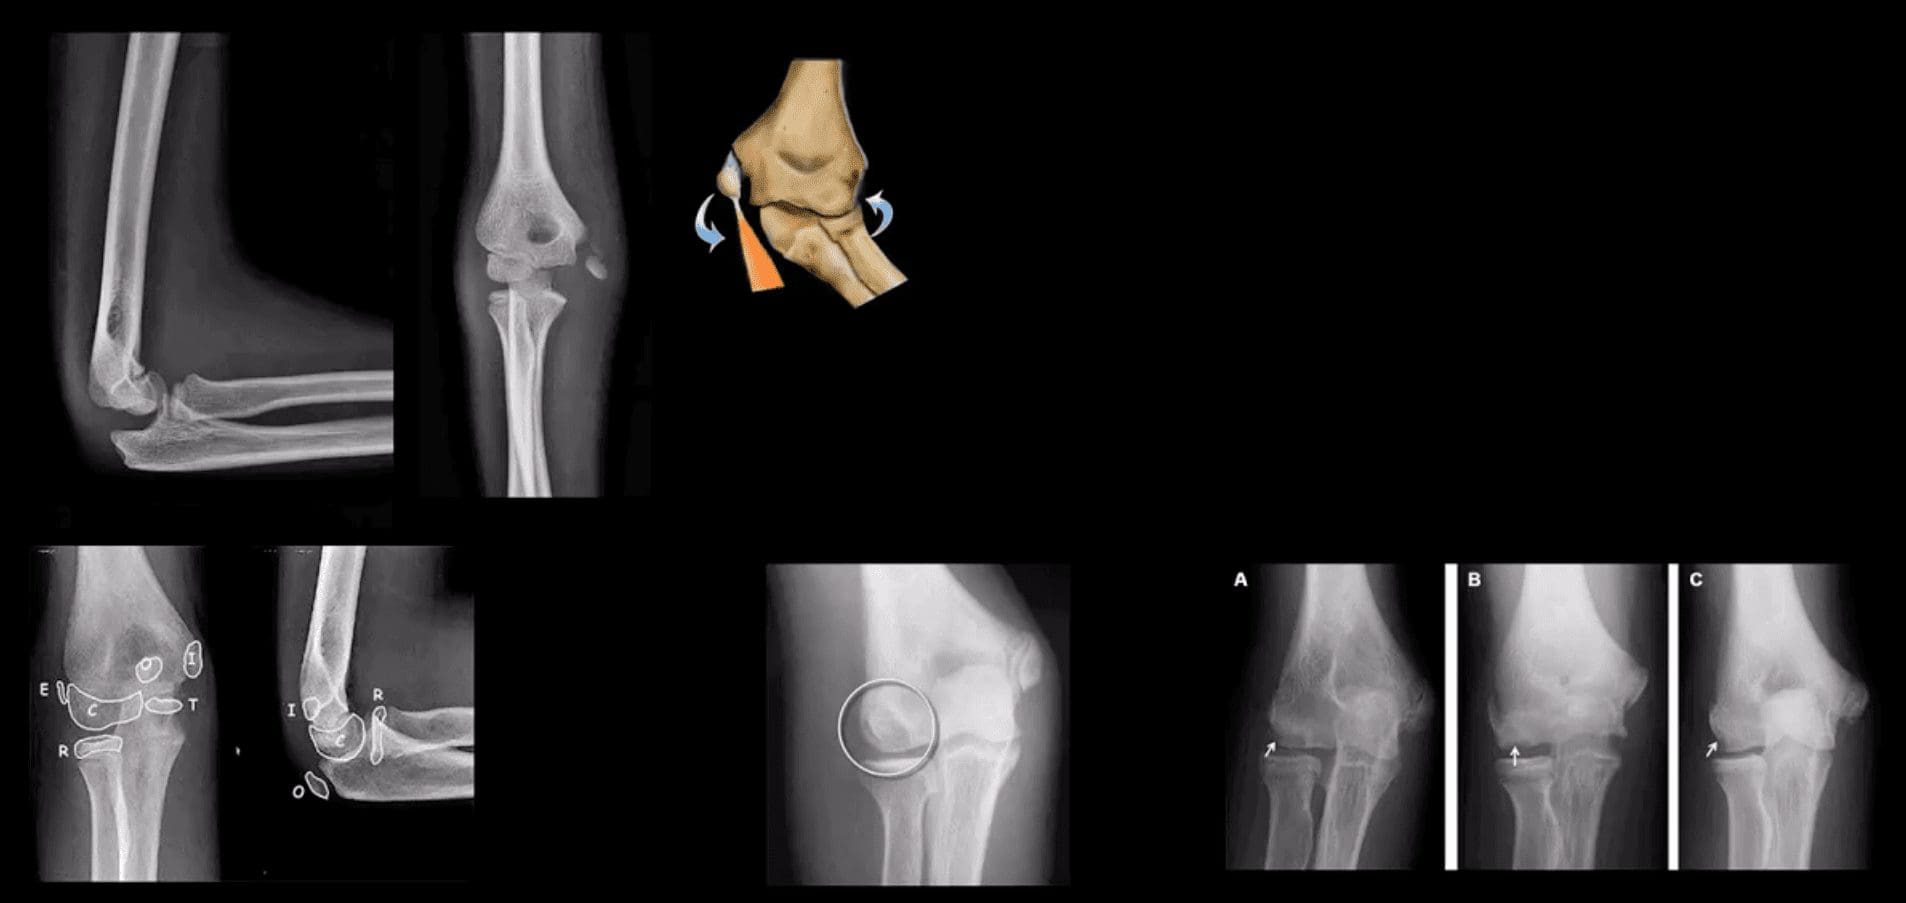

- Radial head (RH) Fx: Mason classification helps to determine the degree of complexity and mode of treatment

- Type 1- undisplaced is the m/c and stable contained by ligaments. On radiographs can be very subtle and evaluation of abnormal elbow fat pads is critical and often the only diagnostic clue

- Type 2- displaced by 2-mm or > with rotational block

- Type 3- comminuted >2-3 fragments and

- Type4 is presented with RH fx, posterior elbow dislocation and sometimes Coronoid process fracture often d/t Brachialis M avulsion

- Note abnormally displaced anterior fat pad (orange arrow) and the emergence of the posterior fat pad (green arrow) that is usually deep in the olecranon fossa and not seen unless acute hemarthrosis or other effusiondevelopsFat pad signs are most reliable indicators of intra-articular elbow Fx

- Mason type 1 RH Fx can be v. subtle and missed. Radiographic search should involve a

close evaluation of positive fat pad signs. Note anterior fat pad displacement aka Sail sign and the presence of the post fat pad d/t acute bleed

- Supracondylar Fx: this is the M/C elbow Fx in children.

- Especially, the un-displaced types 1(top right) is difficult to Dx. Abnormality of “fat pads” and anterior humeral line and radiocapitella line disturbance are often most reliable

- Difficulty in diagnosis may stem from multipleapophysis about the elbow (see CRITOE)